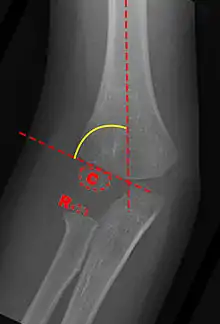

Carrying angle can be evaluated through AP view of the elbow by looking at the Baumann’s angle.[3] There are two definitions of Bowmann's angle:

The first definition of Baumann's angle is an angle between a line parallel to the longitudinal axis of the humeral shaft and a line drawn along the lateral epicondyle.

Another definition of Baumann's angle is also known as the humeral-capitellar angle. It is the angle between the line perpendicular to the long axis of the humerus and the growth plate of the lateral condyle. Reported normal values for Baumann's angle range between 9 and 26°.[7] An angle of more than 10° is regarded as acceptable.[7]